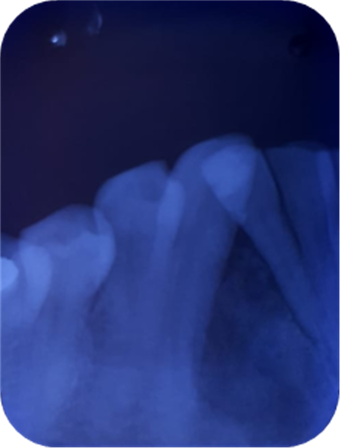

Imagen 4. Oclusal Inferior.

El diagnóstico y tratamiento oportuno que se debe tener frente a las neoplasias odontogénicas que son frecuentes en la consulta odontológica, y la mayoría de casos pasa desapercibido nos hacen tomar conciencia de lo importante de tratar , guiar a los pacientes que visitan la unidad de atención odontológica Uniandes a realizarse exámenes complementarios, radiográficos panorámicos, periapicales, oclusales que tienen la posibilidad de demostrar una visión más clara de las estructuras dentarias vecinas, previniendo desarrollos o formaciones de neoplasias ya que, las radiografías las intraorales periapicales, oclusales demuestra mayor fidelidad dimensional en comparación a la panorámica detectando oportunamente patologías que son asintomáticas.

Los exámenes radiográficos son de gran valor en el diagnóstico oportuno de neoplasias odontógenas principalmente las de mayor fidelidad como las radiografías periapicales y oclusales.